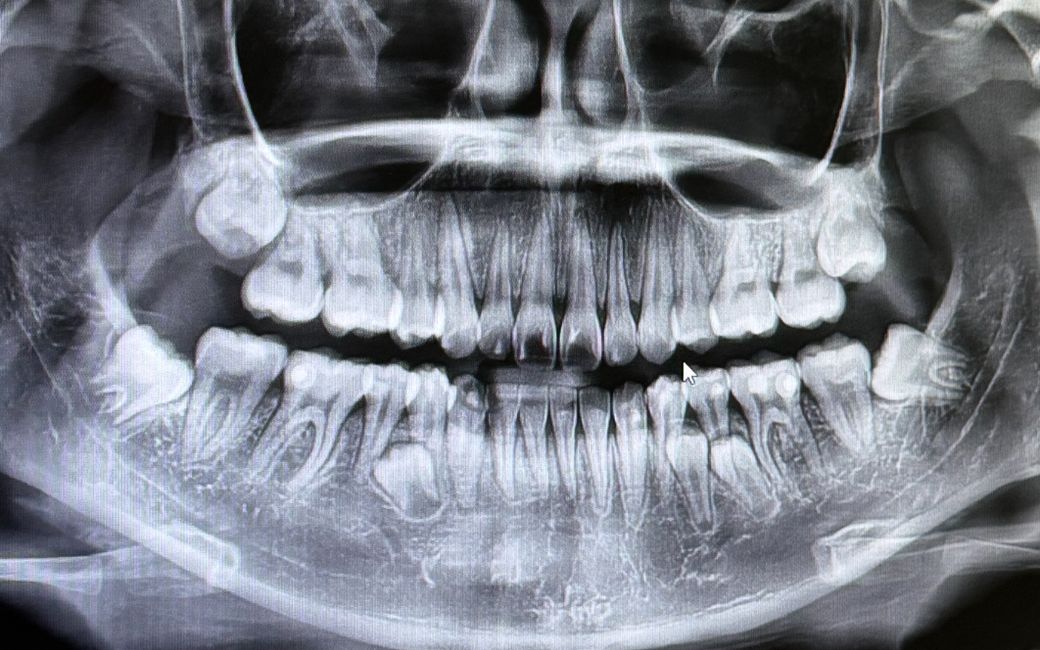

성인 잇몸안에 과잉치 발치 해야하나요?

보시다시피 잇몸 안에 치아가 있는데 과잉치라고 하더라고요 잇몸 밖으로는 나오지 않았고 참고로 현재 교정 후 유지장치 할 계획인데 발치가 필요할까요? 발치한다면 지금 치아에는 영향이 없는 위치인가요?

• 1번 째 사진